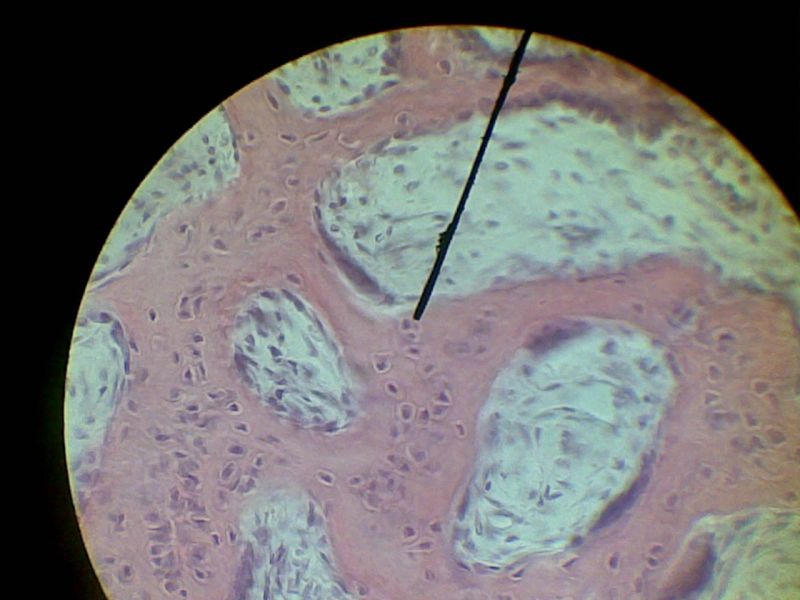

Структура грубоволокнистой костной ткани: наглядные примеры